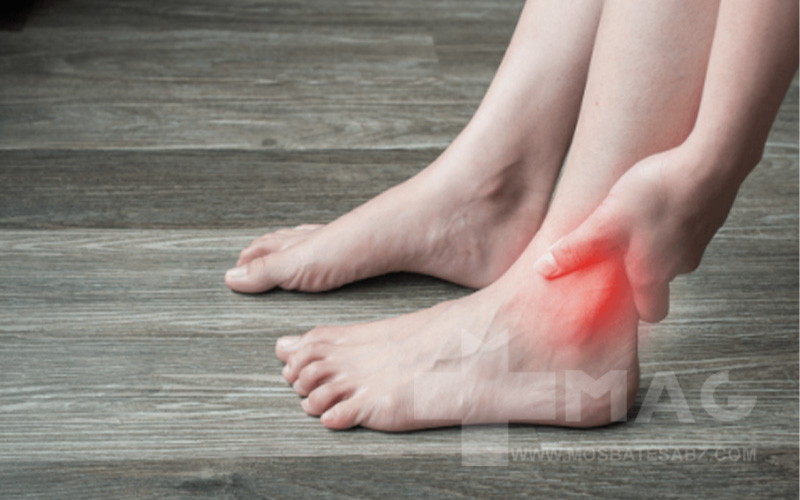

درد مچ پا میتواند به دلایل زیادی رخ دهد. شایعترین علت شامل آسیبها، آرتروز و ساییدگی و پارگی طبیعی است. بسته به علت ممکن است در هر جایی از مچ پا احساس درد یا سفتی کنید. مچ پا شما همچنین ممکن است متورم شود و نتواند وزنی را تحمل کند. معمولا درد مچ پا با استراحت، یخ و داروهای مسکن بدون نسخه بهبود مییابد. یک پزشک متخصص آسیبها و آرتروز را درمان میکند. آسیبهای شدید مچ پا به ویژه شکستگی استخوانها ممکن است نیاز به حراجی داشته باشد. در ادامه به توضیح کامل درد مچ پا هنگام راه رفتن میپردازیم.